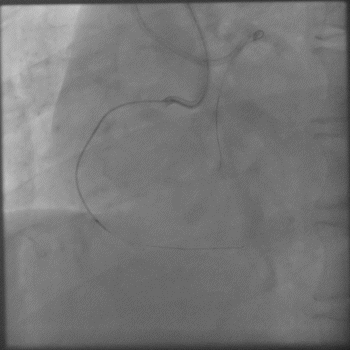

Carlino后导丝仍无法前行;

3.0后扩球囊Base;

P200短距离前行后再也不能前行,

Gaia3磨进2段,进入内膜下,前进艰难;